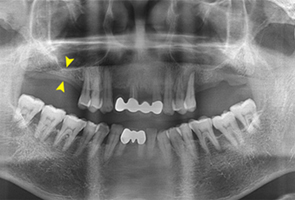

임플란트 시술에서 골이식은 매우 중요합니다. 골이식술은 치조골의 양과 질이 좋지 않을 때 자가골이나 동종골, 이종골 등을 이식하여 임플란트의 지지를 위한 골 재생을 도모하는 술식입니다. 치아가 상실된 지 오래되었거나 만성 치주염 등으로 치조골의 양과 질이 나빠지게 된 경우 골이식이 꼭 필요합니다.

CT검진을 통해 뼈이식에 필요한 뼈의 양과 수술방법을 결정하게 되는데 이때는 다양한 치료 경험을 가진 치료자의 능력 또한 중요합니다.

| 치아가 빠진 지 오래된 경우 | 임플란트 식립 시 심을 공간이 부족한 경우 |

| 치주질환으로 잇몸뼈에 손상이 있는 경우 | 심은 임플란트의 뿌리가 노출 되었을경우 |